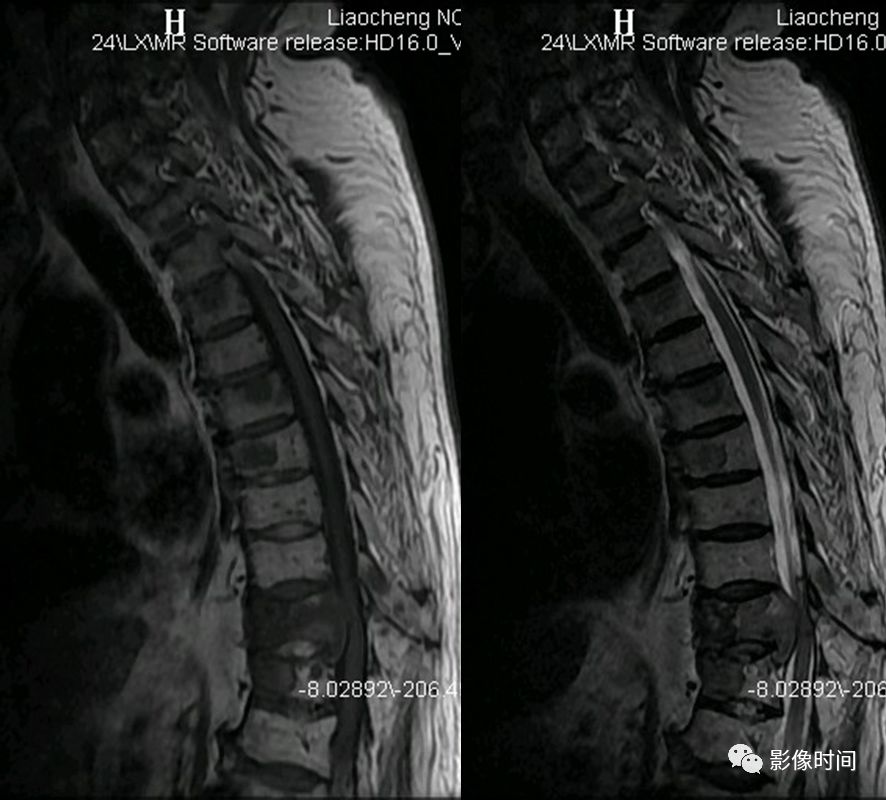

9

MR 液体征

MR 液体征为椎体压缩骨折 MRI 征象,表现为液体敏感序列中在塌陷椎体水肿背景上出现局灶性、线样或三角形更高信号(黄箭),信号强度与脑脊液相仿,T2WI 亦可显示(黄箭)。常提示良性压缩性骨折。

典型病例

67 岁男性,骨质疏松压缩性骨折。MRI 的 T2WI 及脂肪抑制像示两个压缩椎体内可见高信号,与脑脊液相仿(红箭示)。